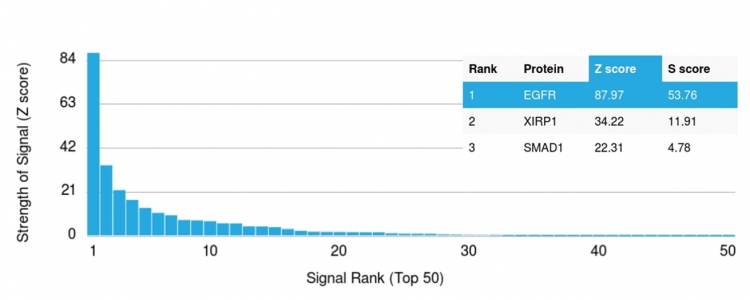

Analysis of Protein Array containing more than 19,000 full-length human proteins using EGFR Mouse Monoclonal Antibody (GFR/2341) Z- and S- Score: The Z-score represents the strength of a signal that a monoclonal antibody (MAb) (in combination with a fluorescently-tagged anti-IgG secondary antibody) produces when binding to a particular protein on the HuProtTM array. Z-scores are described in units of standard deviations (SD's) above the mean value of all signals generated on that array. If targets on HuProtTM are arranged in descending order of the Z-score, the S-score is the difference (also in units of SD's) between the Z-score. S-score therefore represents the relative target specificity of a MAb to its intended target. A MAb is considered to specific to its intended target, if the MAb has an S-score of at least 2.5. For example, if a MAb binds to protein X with a Z-score of 43 and to protein Y with a Z-score of 14, then the S-score for the binding of that MAb to protein X is equal to 29.

This MAb recognizes a protein of 170kDa, identified as EGFR. EGFR is type I receptor tyrosine kinase with sequence homology to erbB-1, -2, -3 -4 or HER-1, -2, -3 -4. It binds to Epidermal Growth Factor (EGF), Transforming Growth Factor-a (TGF-a), Heparin-binding EGF (HB-EGF), amphiregulin, betacellulin and epiregulin. EGFR is overexpressed in tumors of breast, brain, bladder, lung, gastric, head & neck, esophagus, cervix, vulva, ovary, and endometrium. It is predominantly present in squamous cell carcinomas.